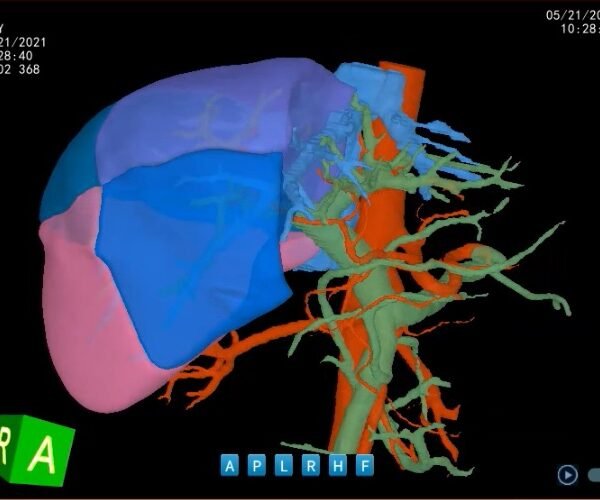

Análisis Hepático tomografía computarizada Intel

Análisis Hepático con IntelliAtlas Pro: Precisión y planificación al alcance de todos LLM Radiologia Análisis Hepático con IntelliAtlas…

Análisis Hepático con IntelliAtlas Pro: Precisión y planificación al alcance de todos LLM Radiologia Análisis…